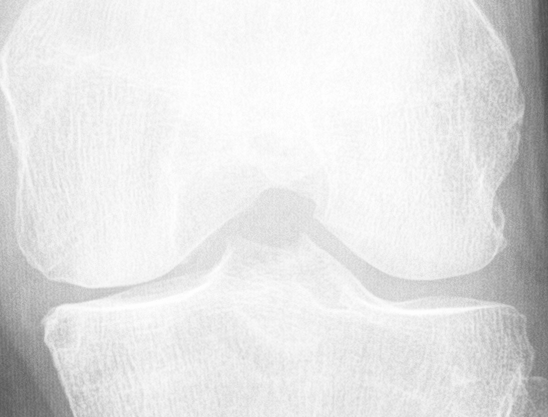

Knee OA develops gradually over years and progresses in stages. In general, the severity of knee OA is divided into five stages. The first stage (stage 0) corresponds to normal healthy knee and the final stage (stage 4) corresponds to the most severe condition (see Figure 2). The most commonly used systems for grading knee OA are the International Knee Documentation Committee (IKDC) system, the Ahlback system, and the Kellgren & Lawrence (KL) grading system. The other widely used non-radiographic knee OA assessment system is WOMAC666Western Ontario and McMaster Universities Osteoarthritis Index, which measures pain, stiffness, and functional limitation. The public datasets, the OAI and the MOST used in this work, are provided with the KL grades and they are used as the ground truth to classify the knee OA X-ray images.

Refer to caption

Figure 2: The Kellgren and Lawrence grading system to assess the severity of knee OA.

The KL grading scale was approved by the World Health Organisation as the reference standard for cross-sectional and longitudinal epidemiologic studies [7, 22, 24, 25]. The KL grading system is still considered the gold standard for initial assessment of knee osteoarthritis severity in radiographs [1, 5, 6, 7]. Figure 2 shows the KL grading system. The KL grading system categorizes knee OA severity into five grades (grade 0 to 4). The KL grading scheme for quantifying knee OA severity from X-ray images is defined as follows [1, 5]:

• Grade 0 : absence of radiographic features (cartilage loss or osteophytes) of OA.

• Grade 1 : doubtful joint space narrowing (JSN), osteophytes sprouting, bone marrow oedema (BME), and sub-chondral cyst.

• Grade 2 : visible osteophytes formation and reduction in joint space width on the antero-posterior weight-bearing radiograph with BME and sub-chondral cyst.

• Grade 3 : multiple osteophytes, definite JSN, sclerosis, possible bone deformity.

• Grade 4 : large osteophytes, marked JSN, severe sclerosis, and definite bone deformity.